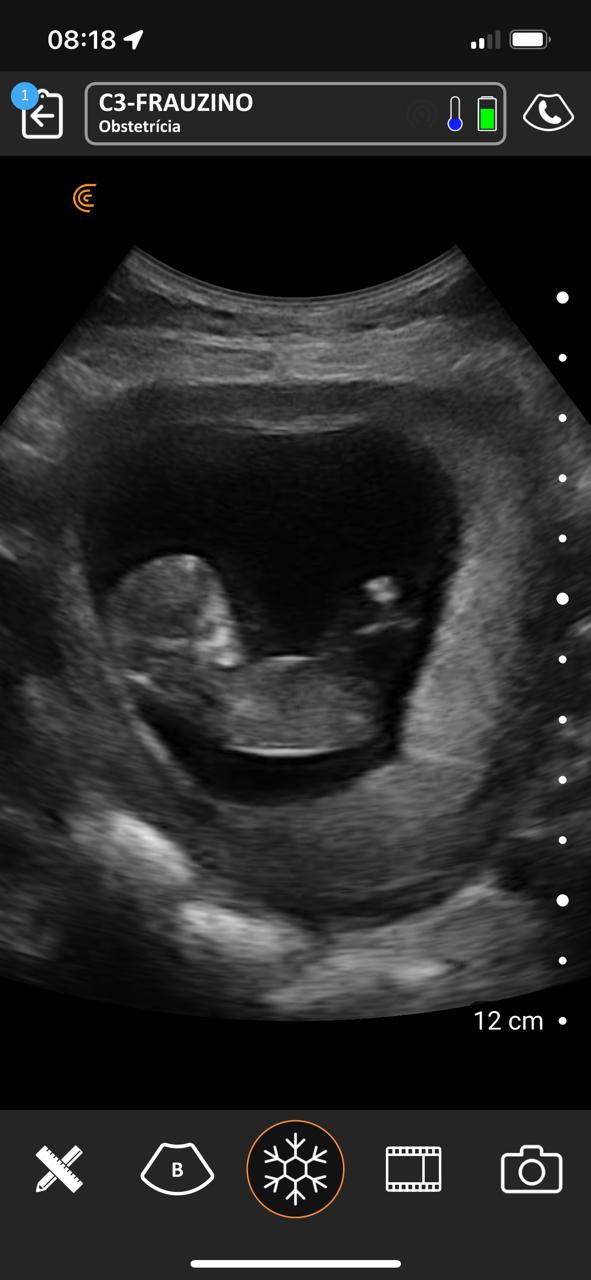

No período compreendido entre 07/03/2023 a 07/03/2025 na Estratégia de Saúde da Família São Francisco ESF-03 e Sol Nascente ESF-07 no município de Porangatu (GO), Brasil realizou-se um total de 8.349 atendimentos médicos, com 769 consultas de pré-natal e 411 ultrassons no local de atendimento de acompanhamento do pré-natal de risco habitual com aparelho portátil de bolso, sem fio, tecnologia Clarius C3 HD3, transdutor convexo, frequência de 2-6 MHz e monitores iPhone-10 e iPad Air 11. Acompanharam alguns atendimentos 12 bolsistas do PMpB dos municípios goianos Bonópolis, Britânia, Campinorte, Mara Rosa, Mundo Novo, Mutunópolis, Niquelândia, Nova Veneza, Santa Tereza de Goiás, São Miguel do Araguaia e do Pará Santana do Araguaia. Os bolsistas não tinham conhecimentos prévios sobre a PoCUS, disseram que sua formação nessa ferramenta durante o PMpB foi satisfatória e caso tivessem um aparelho sentem confiança em realizar o procedimento tanto na Unidade Básica de Saúde quanto nos domicílios, acreditaram que a formação básica recebida foi alcançada e concordam totalmente que a ultrassonografia no local de atendimento poderia estar dentro da formação especializada em medicina de família e comunidade e entenderam que no pré-natal de risco habitual é uma ferramenta que pode mudar sua conduta.

Nos acompanhamentos das consultas de pré-natal, dos 411 ultrassons realizados, 19 foram de diagnóstico gestacional e datação da idade gestacional, sendo 13 com idade gestacional menor de 14 semanas, uma na 24ª e outra na 29ª semana. Houve duas gestações gemelares que foram acompanhadas conjuntamente com o alto risco. A média de idade das gestantes foi de 26 anos e o da idade gestacional de 22 semanas e 2 dias. Os bolsistas realizaram um total de 188 ultrassons e após a familiarização teórica e prática, foram capazes de identificar 10 tópicos como situação, apresentação, dorso, batimento cardíaco fetal, movimentos fetais, órgãos internos (ao menos 1 estrutura), biometria (ao menos diâmetro biparietal e comprimento do fêmur), placenta, líquido amniótico, cordão umbilical, datar e descrever o procedimento.